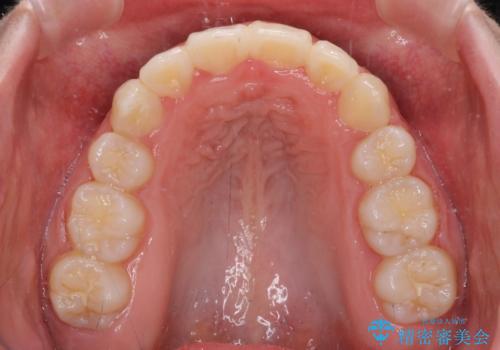

著しい叢生と顎骨のズレ ワイヤー装置による抜歯矯正

- 前歯の著しい叢生や八重歯を気にして来院された患者様です。

上下の顎がずれており、上下の正中は歯1本分の差がありました。

上下左右の小臼歯4本を抜歯し、極力正中を合わせるように矯正治療を始めていくこととしました。